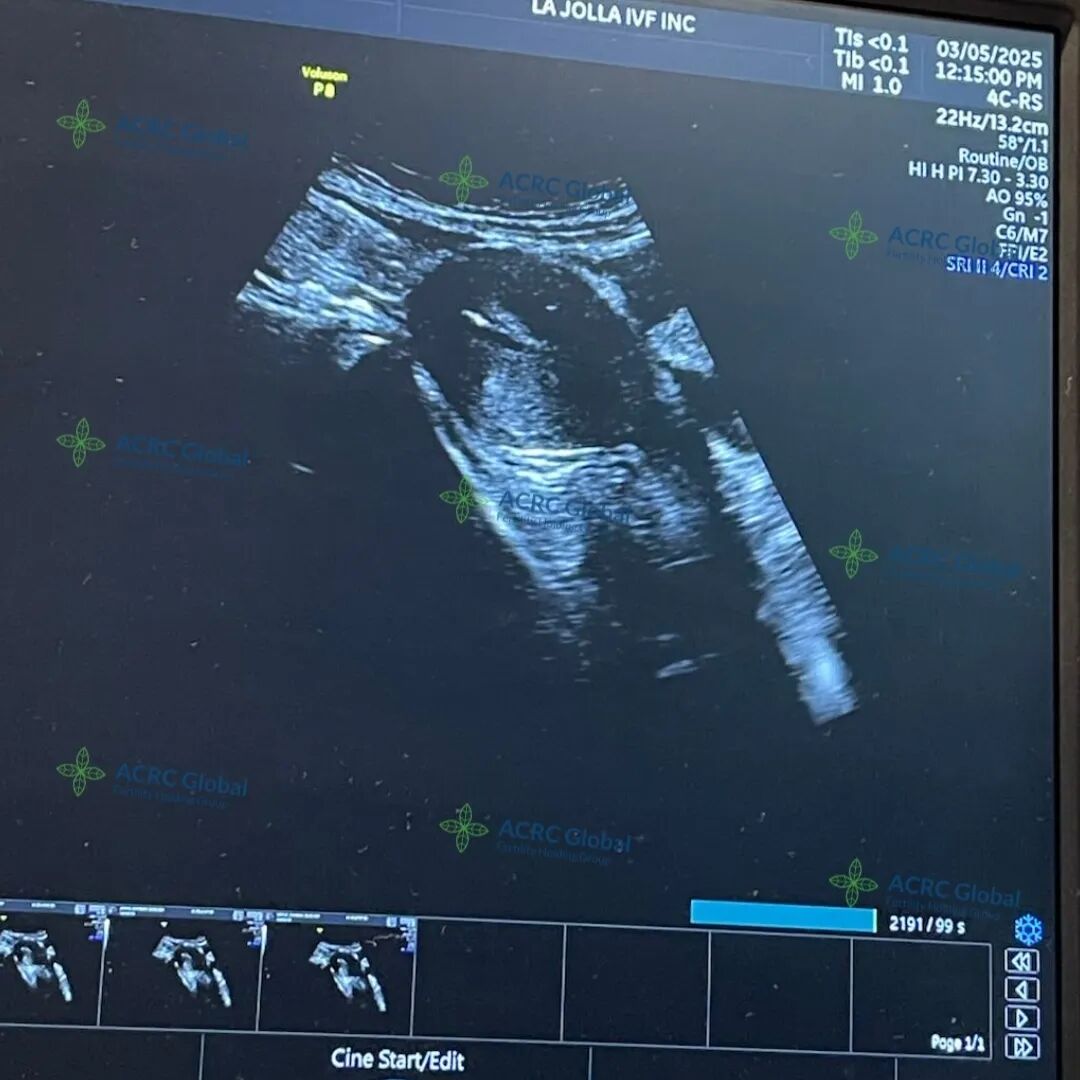

作为一位已经育有两个可爱男孩的母亲,她深知生命的可贵,也体会过迎接新生命的喜悦。因此当她决定成为爱妈,帮助另一对准父母实现他们的生育梦想时,得到了未婚夫和孩子们最温暖的支持。她的未婚夫全程陪伴在侧,给予她坚定的鼓励,让整个移植过程显得更加温馨、轻松与自在。

而远方的准父母也满怀期待,迫不及待地迎接他们第一个宝宝的到来,幸福的旅程即将开启!

这一次,她再次选择ACRC,开启二胎计划,并成功匹配了爱妈J。在充分沟通与准备后,她决定移植另一个男宝宝胚胎,期待能顺利迎来第二个小天使。整个过程中,她对爱妈 J 充满信任,也对这次孕期充满期待,希望宝宝健康成长,一切顺利如愿。